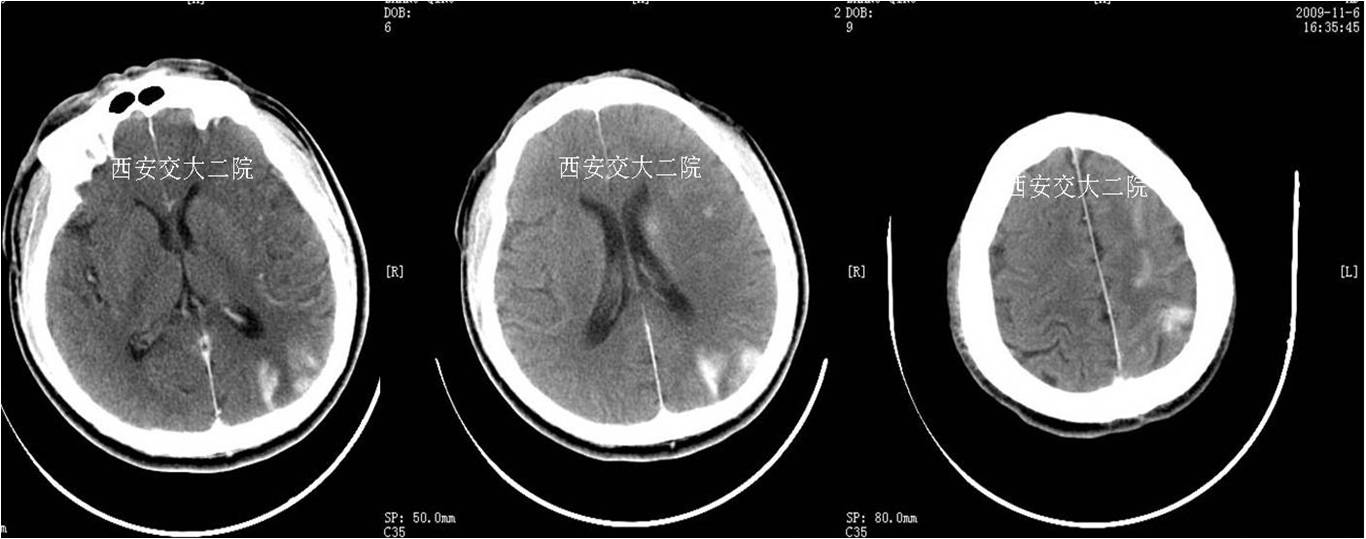

术前CT(病后1h)

术前DWI

术后即刻病情及脑CT

术后24小时脑CT

术后病情变化

术后24h仍呈混合性失语,右侧肢体肌力Ⅴ-级。

术后48h言语恢复正常,右侧鼻唇沟略浅,四肢肌力Ⅴ级,转心外科继续准备手术。